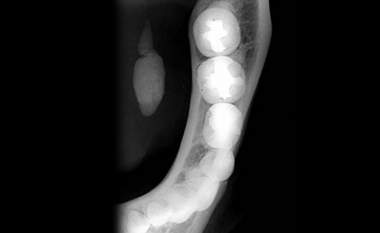

Een ander vaak voorkomend probleem is zwelling t.g.v. stuwing in de klier door steenvorming. Dit zien we vaak bij de speekselklier die ter hoogte van de kaakhoek ligt. Een kenmerk is, dat de klier snel opzwelt tijdens de maaltijd en soms zo groot wordt al een ei. Na de maaltijd neemt de zwelling weer geleidelijk af.

Bij de diagnostiek wordt bekeken waar de steen ligt. De steen kan liggen in de afvoerbuis welke in de mondbodem loopt of in de klier. Als de steen op een gunstige plek ligt in de afvoerbuis kan meestal volstaan worden met het verwijderen van de steen. In de meeste gevallen kan dit onder plaatselijke verdoving. Als de steen in de klier ligt, moet meestal de speekselklier verwijderd worden. Dit gebeurt onder narcose via een snede in de hals ter hoogte van de kaakhoek.